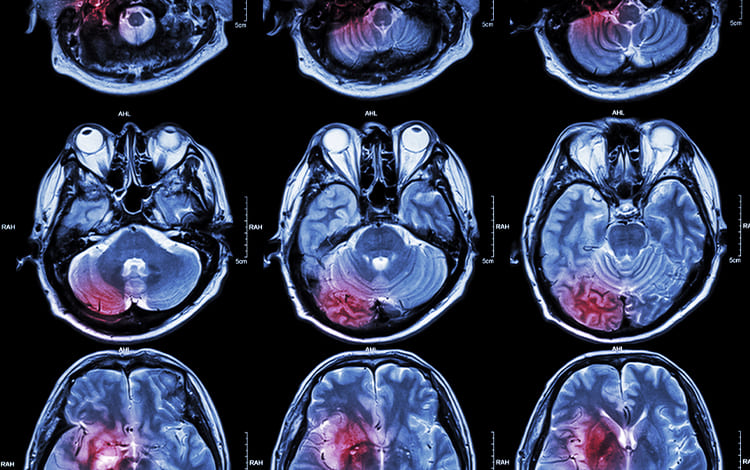

Los tumores de cabeza y cuello pueden involucrar desde lesiones en la piel, senos paranasales, cavidad oral, labio, laringe, glándulas salivales.